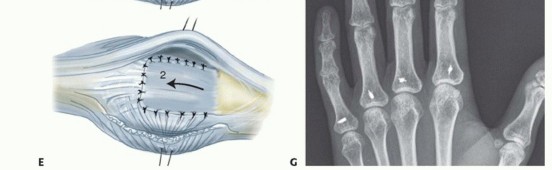

Once the extensor mechanism of each joint is exposed, the degree of ulnar subluxation of the EDC tendon is assessed. To access the joint space, a longitudinal incision is made through the attenuated radial sagittal band, parallel to the radial border of the extensor tendon. The EDC tendon is then sharply retracted ulnarly, exposing the underlying dorsal joint capsule.

The dorsal capsule is incised longitudinally, revealing the synovial cavity. In the rheumatoid patient, the joint will be engorged with hyperplastic, friable, and highly vascular pannus. A meticulous synovectomy is performed using a combination of sharp excision with a #15 blade, fine rongeurs, and a motorized synovial shaver if necessary.

The surgeon must systematically clear the pannus from the dorsal pouch, the collateral ligament recesses, and, crucially, the volar pouch beneath the metacarpal head. To access the volar pouch, the proximal phalanx is gently volar-flexed, and a small, curved rongeur is passed volarly to extract the hidden synovial tissue. Extreme care must be taken to avoid scoring or damaging the preserved articular cartilage during this process. The collateral ligaments should be inspected; while often stretched, they are rarely completely ruptured and should be preserved.

Figure 7: Exposure of the joint space following incision of the radial sagittal band. The hyperplastic synovium (pannus) is visualized prior to meticulous excision.

Figure 8: Intraoperative view highlighting the severe ulnar subluxation of the extensor tendons into the intermetacarpal valleys, a hallmark of advanced inflammatory soft-tissue failure.